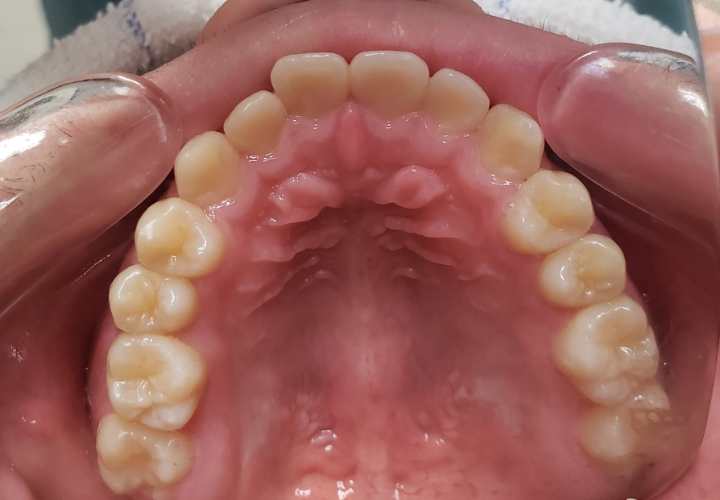

治療後

13歳頃、永久歯列になったところで、1期治療終了。後は親御さんが希望されたため、メンテナンスに移行し、高校生になったら下の親知らずを抜歯することにしました。